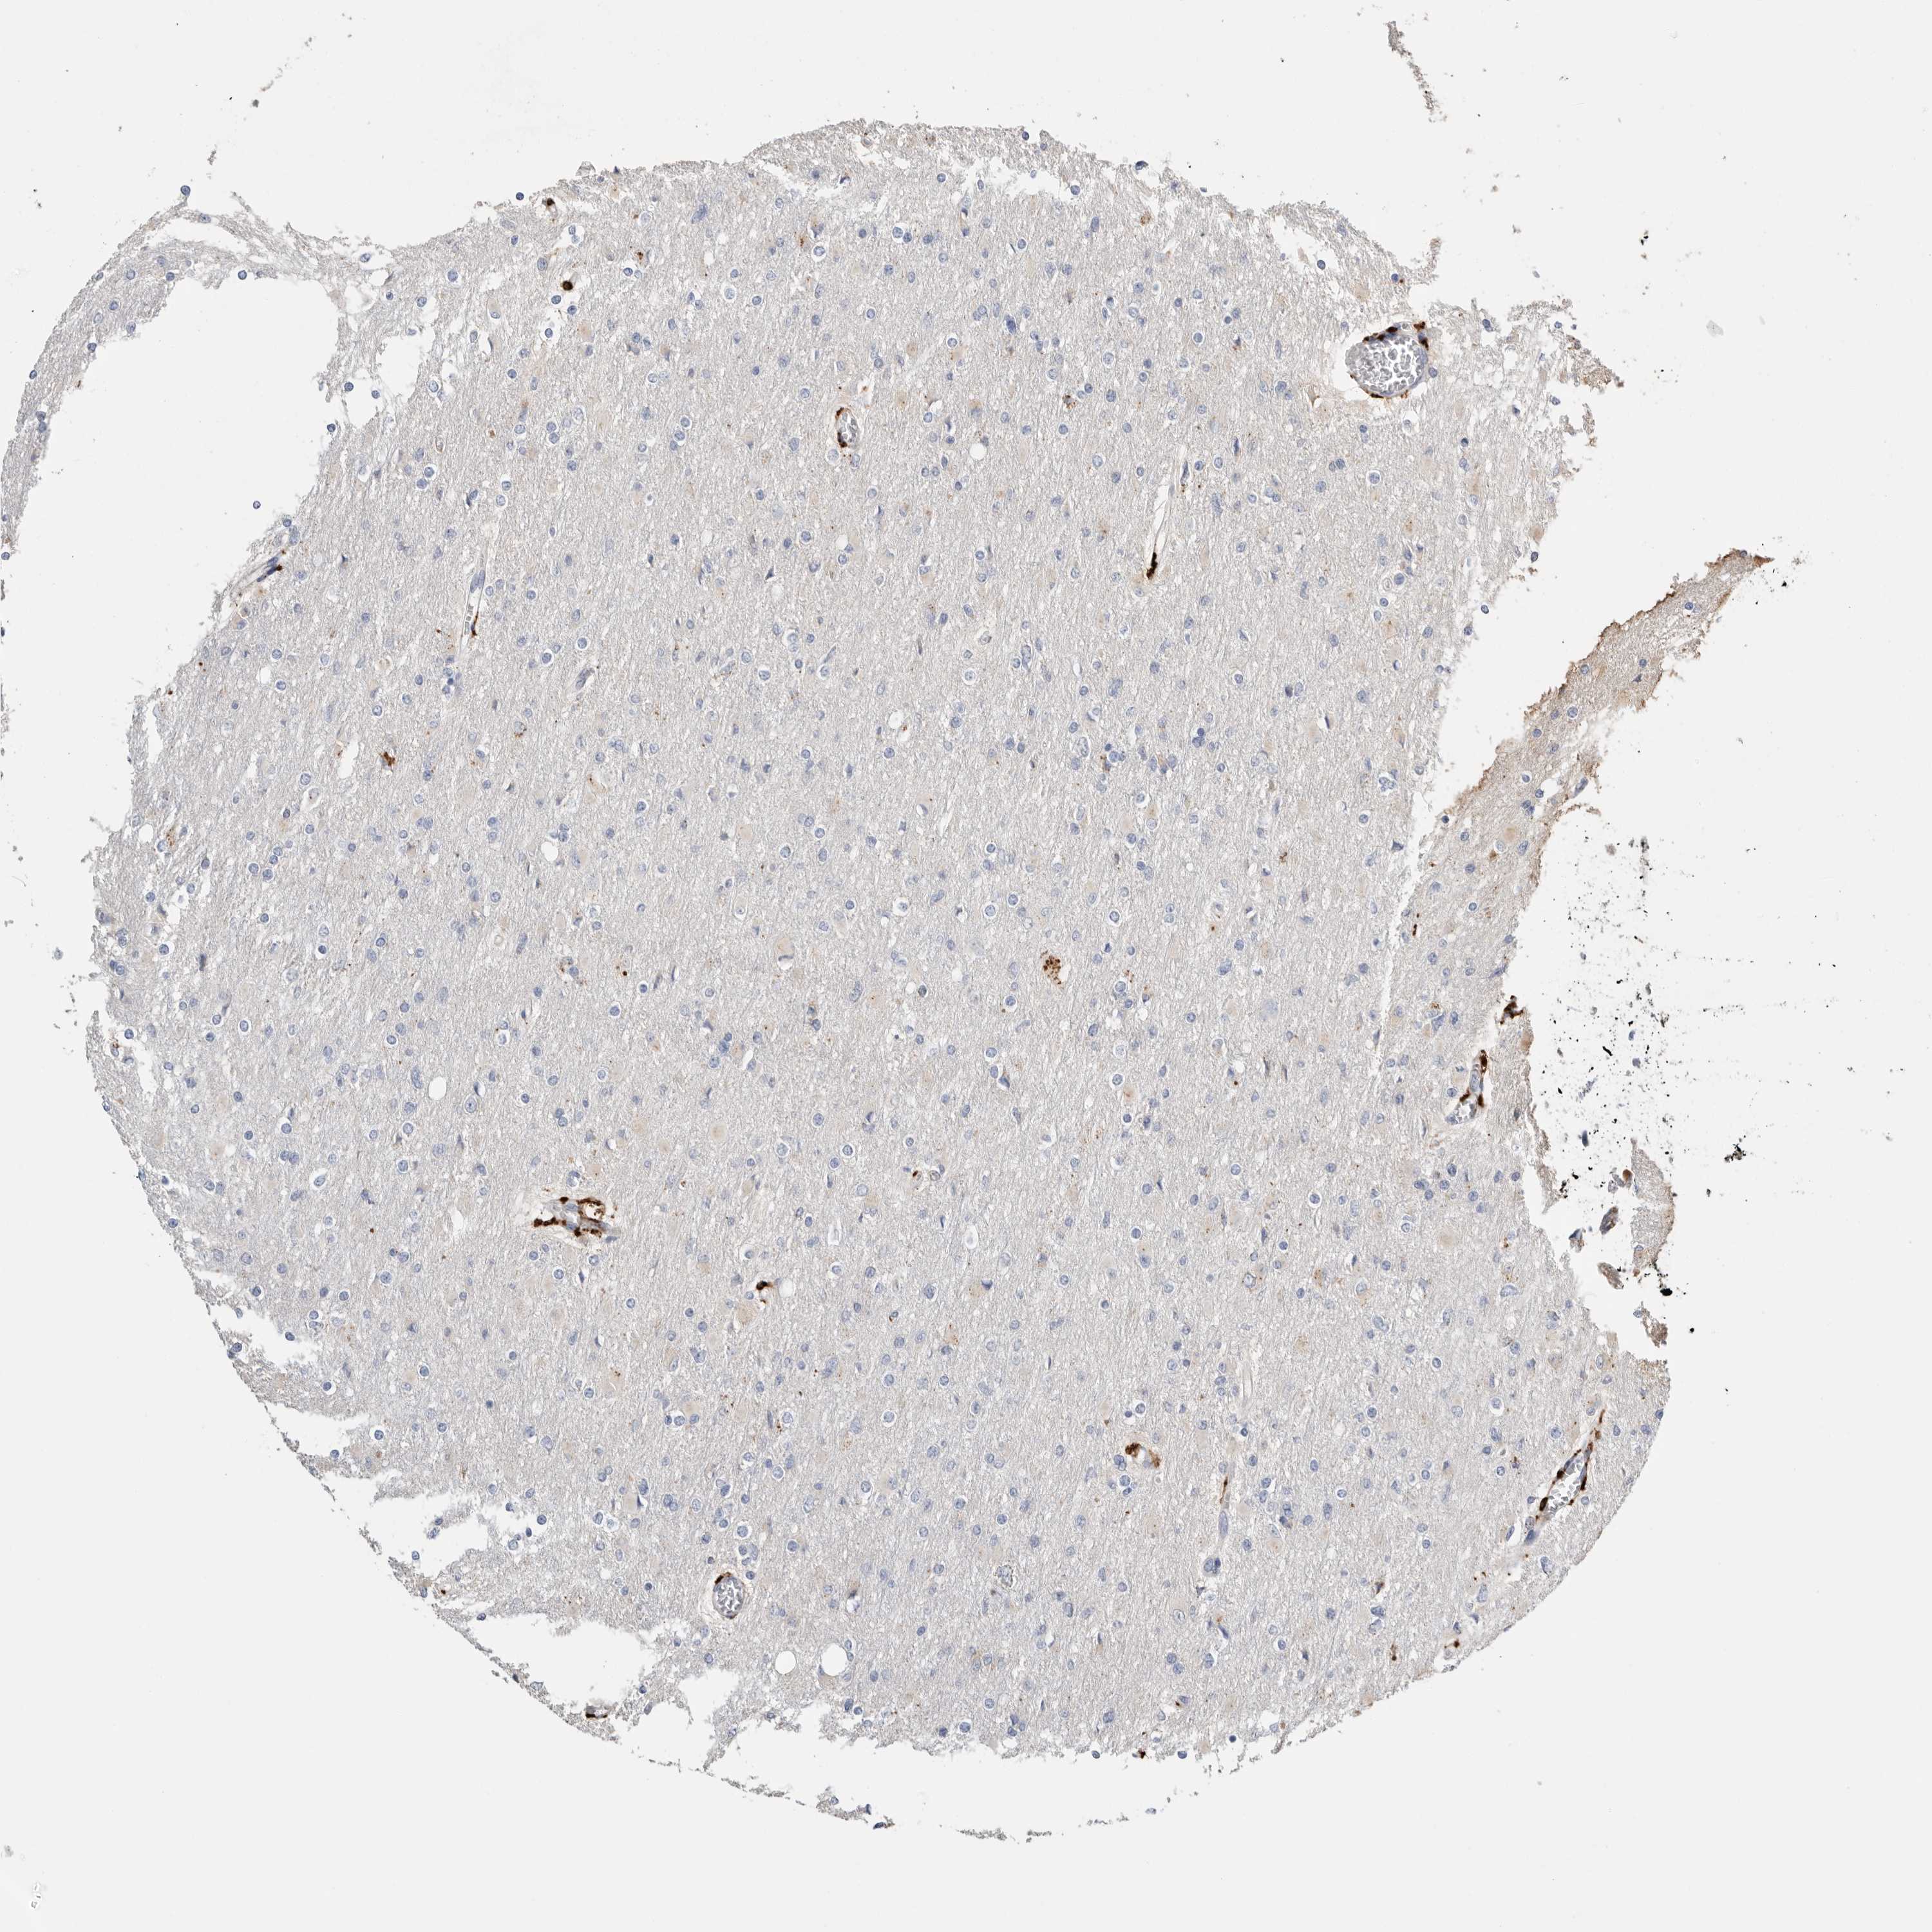

GLIOMA - Protein expressioni

A mouse-over function shows sample information and annotation data. Click on an image to view it in a full screen mode. Samples can be filtered based on level of antibody staining by selecting one or several of the following categories: high, medium, low and not detected. The assay and annotation is described here.

Note that samples used for immunohistochemistry by the Human Protein Atlas do not correspond to samples in the TCGA dataset.

Antibody stainingi

Antibody staining in the annotated cell types in the current human tissue is reported as not detected, low, medium, or high, based on conventional immunohistochemistry profiling in selected tissues. This score is based on the combination of the staining intensity and fraction of stained cells.

Each image is clickable and will lead to virtual microscopy that enables deeper exploration of all samples and also displays staining intensity scores, fraction scores and subcellular localization as well as patient and tissue information for each sample.

Antibody HPA025226

Antibody CAB019296

Glioma, malignant, High grade

Glioma, malignant, Low grade